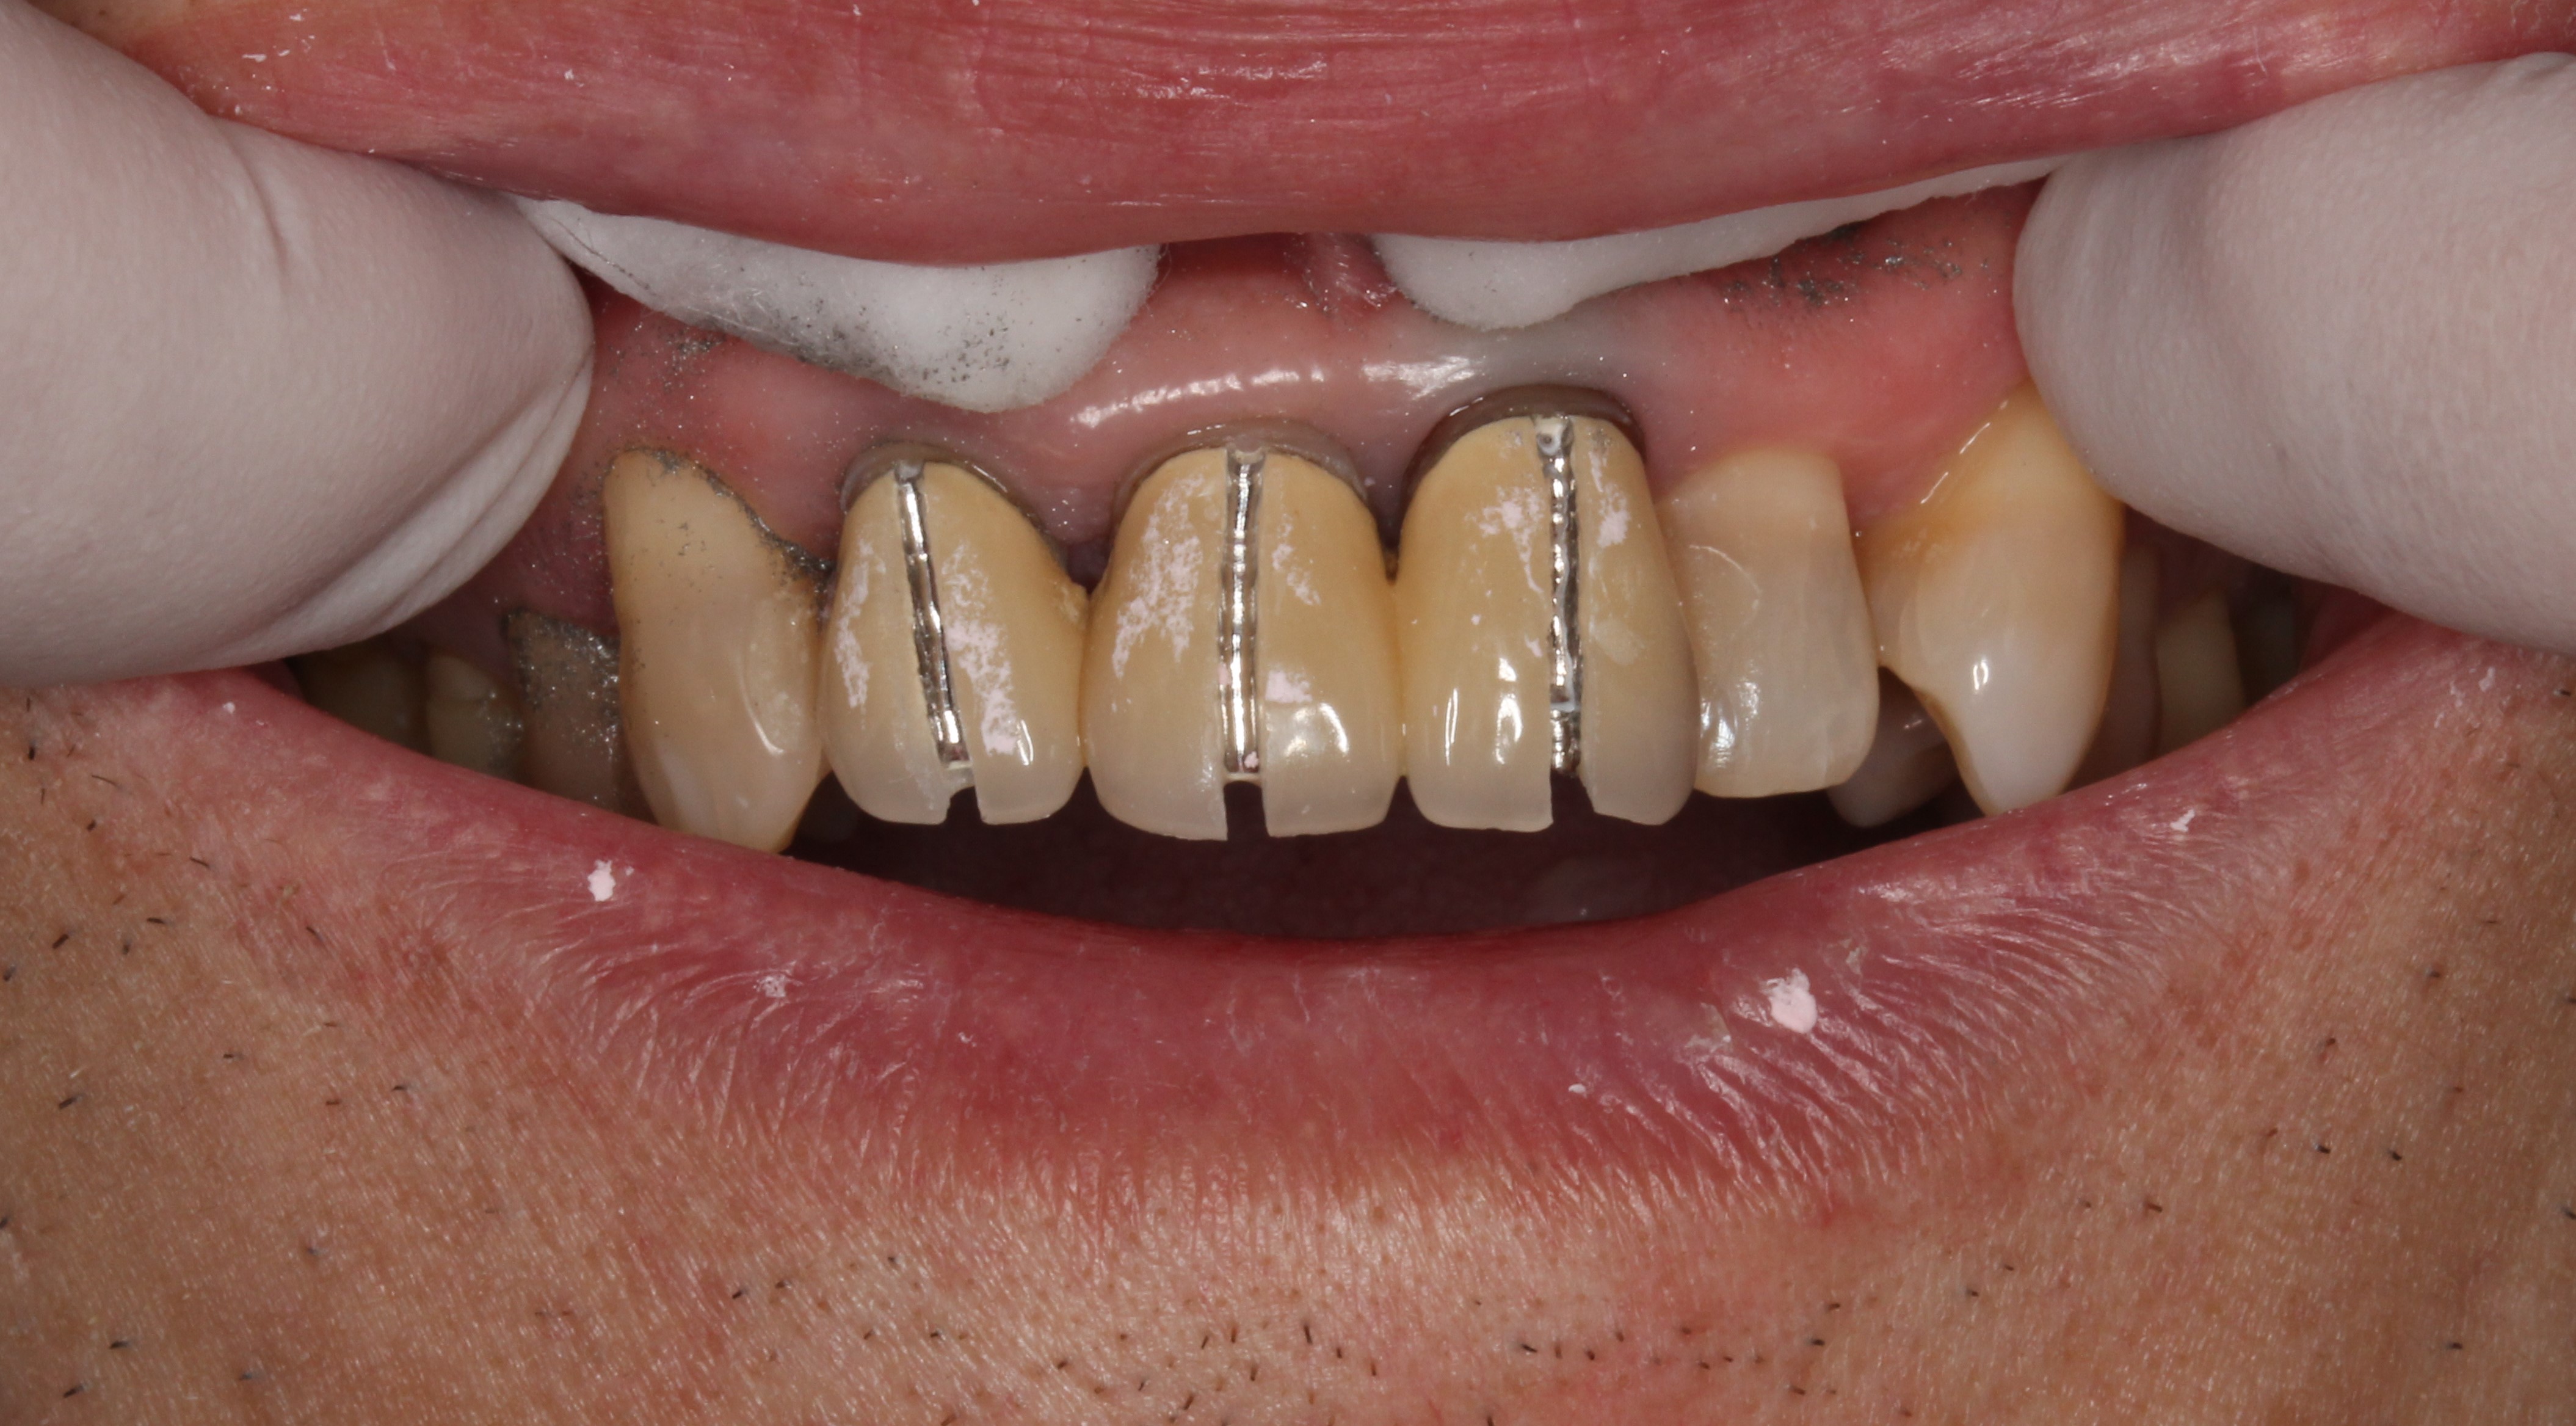

また今回の差し歯を外していくと、

スリットを入れて削って外していきます。

前歯は連結といって繋がっているのですが、

外れました。

1本だけメタルコアが残っています。